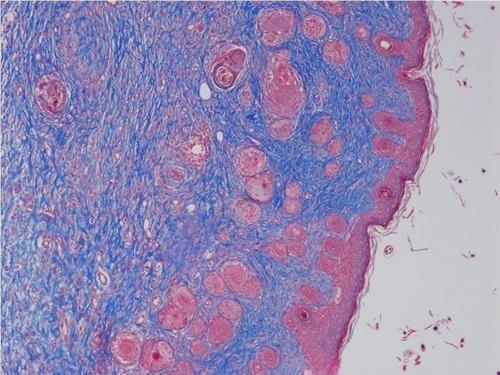

3.小鼠皮肤损伤masson